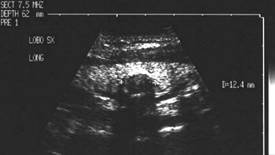

Chiste coloide

Sonda convexa de 5.0 MHz,

Sonda liniara de 10.0 MHz, proiectie trasversala si longitudinala a lobului

stang.

Pacienta de 28 ani. Voluminoasa tumefactie a lobului

stg., marcant hipoecogena, cu intarire posterioara, de 38x45x69mm.

La aspiratie, circa 60 cc de coloid foarte dens.